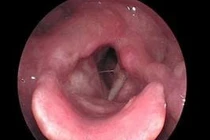

Tại Bệnh viện Đa khoa Tâm Anh TP HCM, GS.TS.BS Trần Phan Chung Thủy, Giám đốc Trung tâm Tai Mũi Họng cho biết, kết quả nội soi họng thanh quản cho thấy hai dây thanh của ông Sang sung huyết, khối sùi dây thanh môn mép trước.